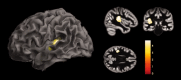

Noninvasive brain imaging methods provide useful information on cerebral involution and degenerative processes. Here we assessed cortical degeneration in 20 nondemented patients with Parkinson's disease (PD) and 20 healthy controls using three quantitative neuroanatomical approaches: voxel-based morphometry (VBM), cortical folding (BrainVisa), and cortical thickness (FreeSurfer). We examined the relationship between global and regional gray matter (GM) volumes, sulcal indices, and thickness measures derived from the previous methods as well as their association with cognitive performance, age, severity of motor symptoms, and disease stage. VBM analyses showed GM volume reductions in the left temporal gyrus in patients compared with controls. Cortical folding measures revealed significant decreases in the left frontal and right collateral sulci in patients. Finally, analysis of cortical thickness showed widespread cortical thinning in right lateral occipital, parietal and left temporal, frontal, and premotor regions. We found that, in patients, all global anatomical measures correlated with age, while GM volume and cortical thickness significantly correlated with disease stage. In controls, a significant association was found between global GM volume and cortical folding with age. Overall these results suggest that the three different methods provide complementary and related information on neurodegenerative changes occurring in PD, however, surface-based measures of cortical folding and especially cortical thickness seem to be more sensitive than VBM to identify regional GM changes associated to PD.